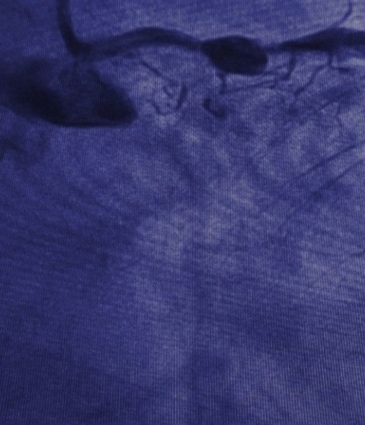

Exercise tests such as the ETT and ESE assess how your heart performs under physical stress. At Dr Sayan Sen’s private cardiology clinics in London these tests help diagnose coronary artery disease, arrhythmias and other exercise-induced cardiac concerns.

Exercise tests monitor your heart’s response to controlled physical exertion, providing crucial data for diagnosis and treatment. Two common forms are the Exercise Tolerance Test (ETT) and the Stress Echocardiogram (ESE).

An ETT involves walking on a treadmill while your heart rhythm, blood pressure and symptoms are monitored. An ESE combines treadmill exercise with ultrasound imaging of the heart before and after exertion. These tests are particularly useful in identifying reduced blood flow to the heart, abnormal rhythms, or causes of exertional chest pain and breathlessness.